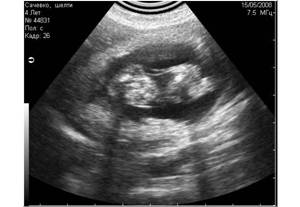

Рис3. Помехи, вызванные плохим выбриванием животного (продольные полосы слева). |